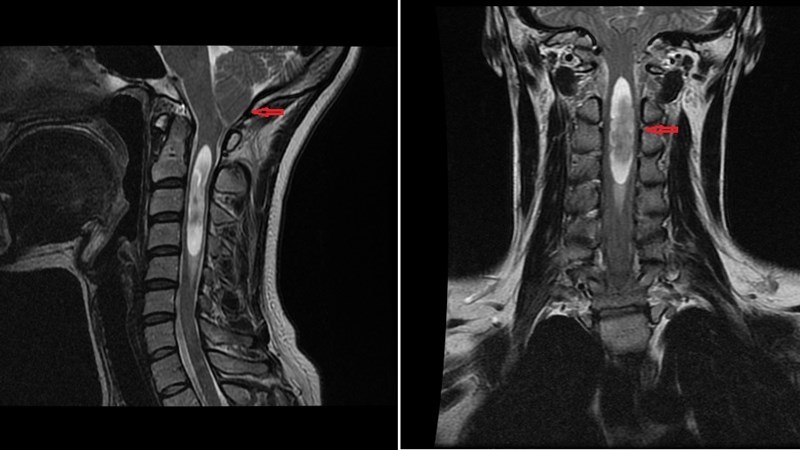

Аномалия Арнольда-Киари: MRI снимки